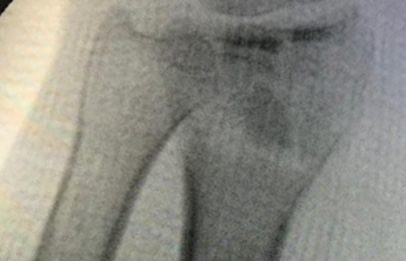

Cirugías de Muñecas

Los procedimientos más comunes en cirugía de la mano son aquellos destinados a reparar traumatismos, incluyendo lesiones de tendones, nervios, vasos sanguíneos, y articulaciones; huesos fracturados; y quemaduras, cortes, y otros daños de la piel.